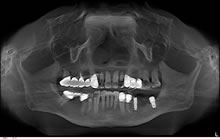

CT検査の結果より、当院では左下に短いショートインプラント(7mm)を使用することにより治療が十分可能と診断し、治療を開始しました。 インプラントを2本埋入し、しっかりと骨とインプラントが結合するのを2ヶ月待ち、セラッミクの歯を入れて終了。短いインプラントでも十分に固定され、左側でもしっかり咬んでいただけるようになりました。

【3】インプラント手術後のレントゲン写真